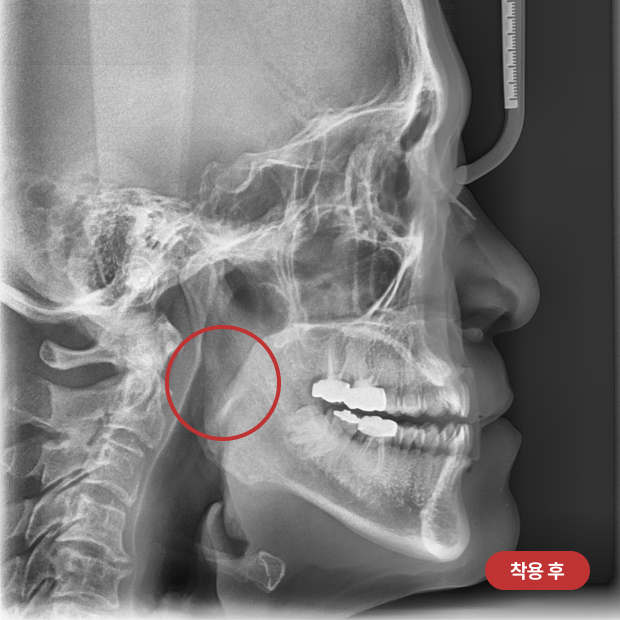

착용 전/후

넓어진 기도를

확인해보세요!

장치를 착용하면서 근기능 훈련을 함께하면 구호흡을 방지하고 비호흡을 유도하며,

아래턱이 앞으로 나와 기도가 넓어지는 효과를 경험할 수 있습니다.

이로 인해 코골이와 수면무호흡의 정도를 줄일 수 있습니다.